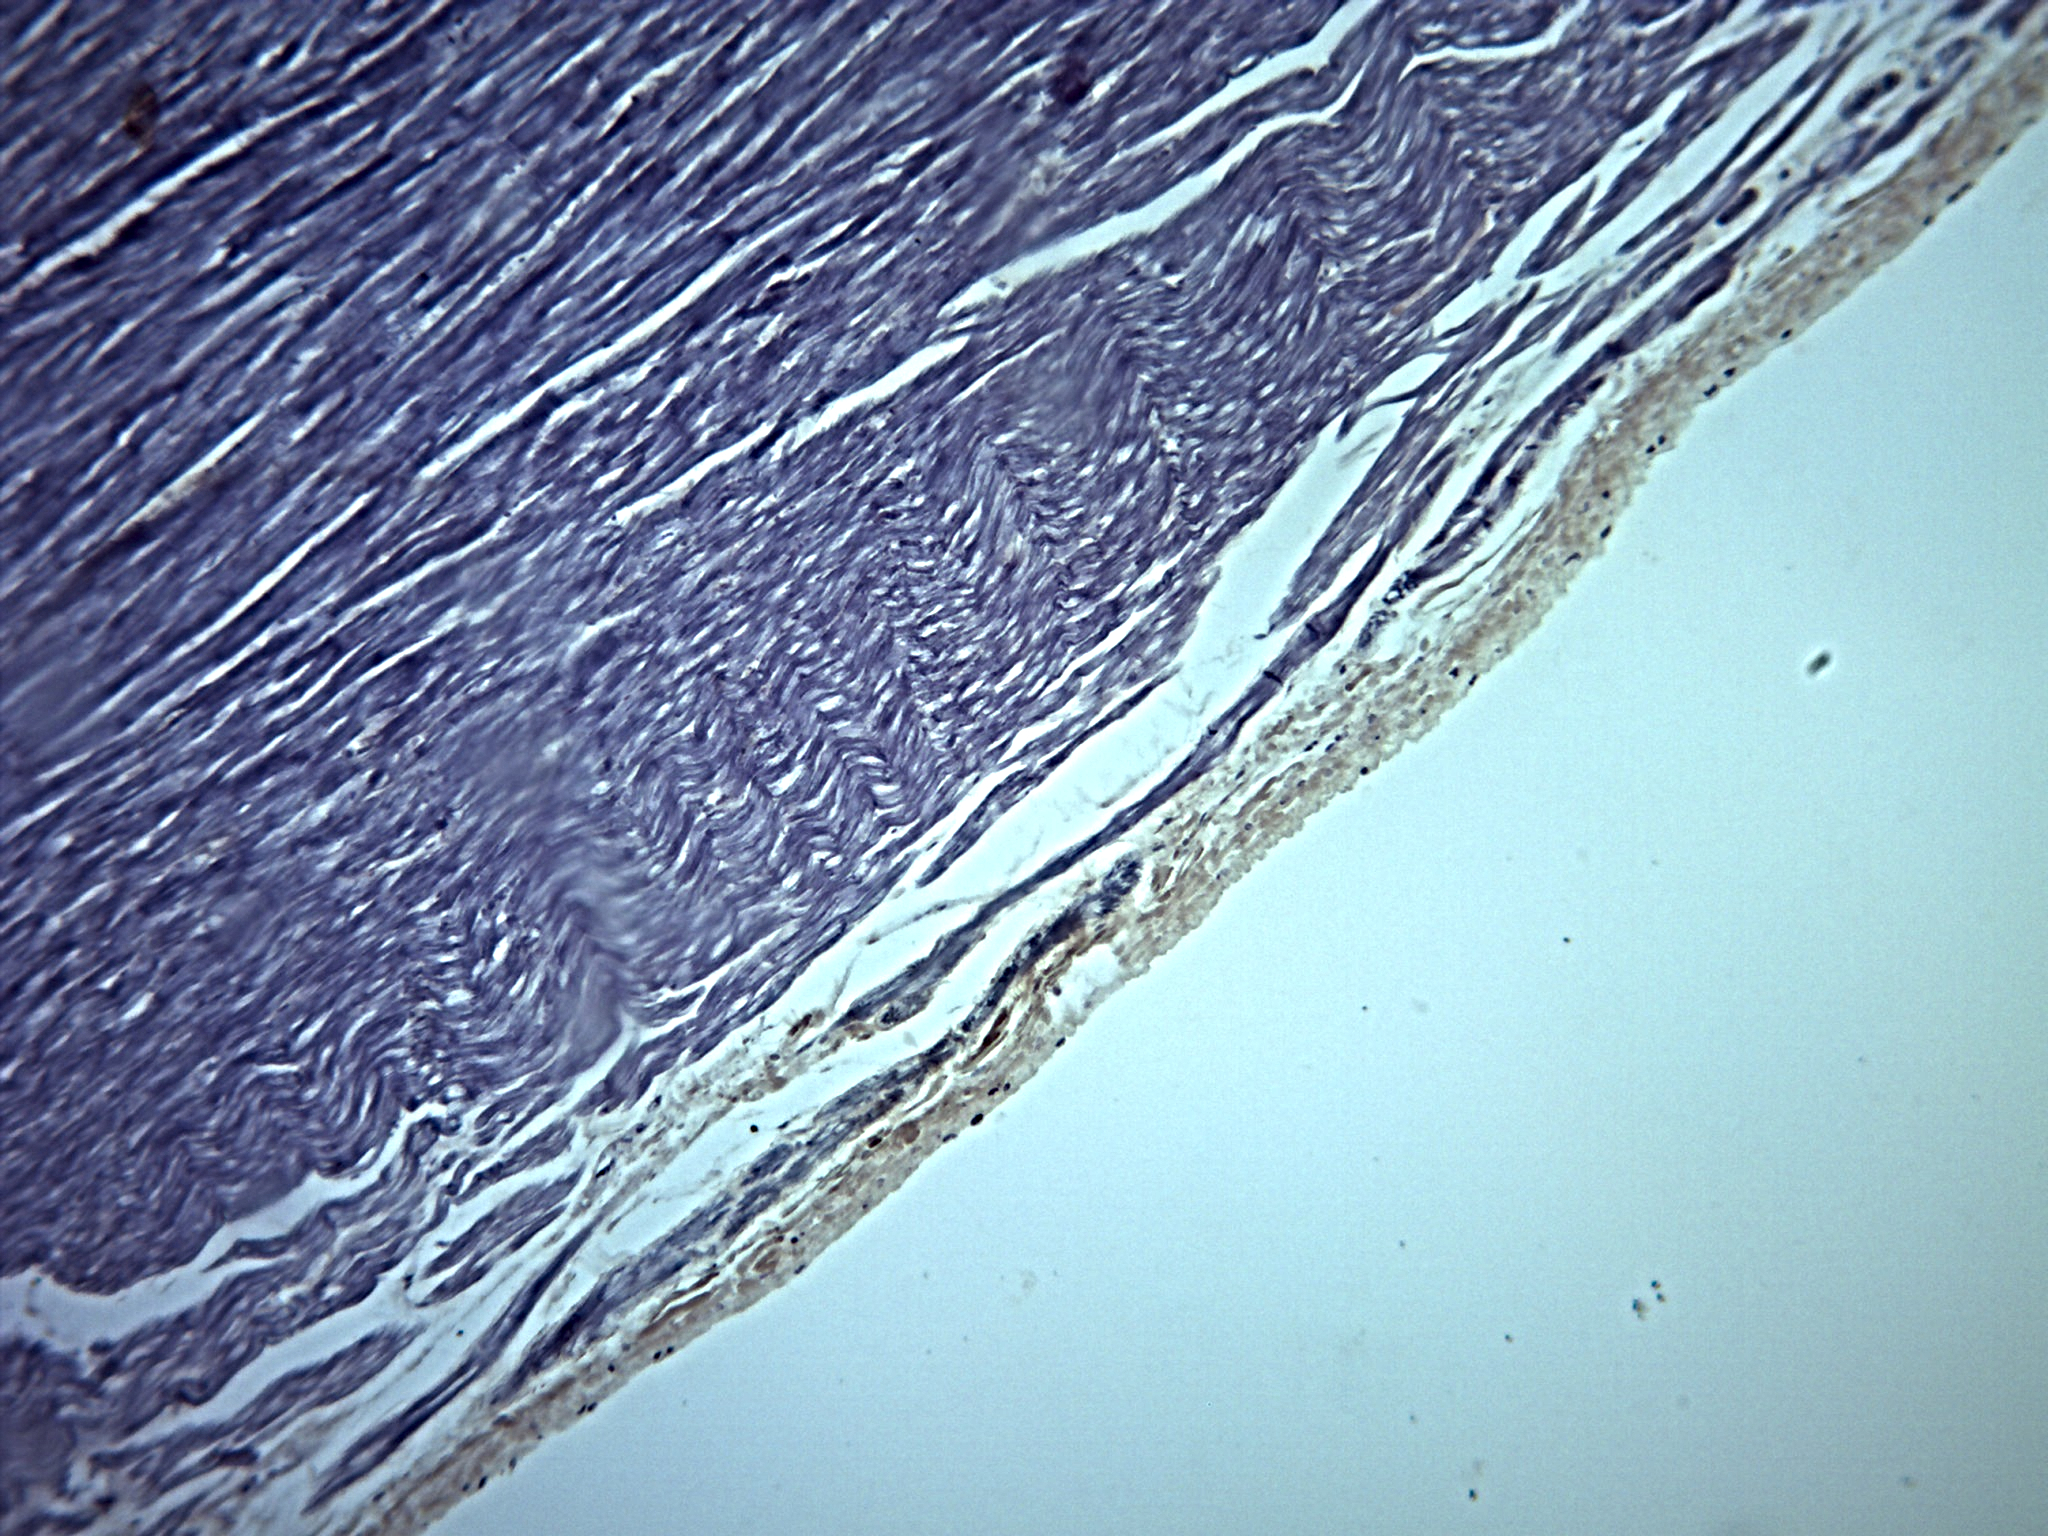

Sistema Circulatório